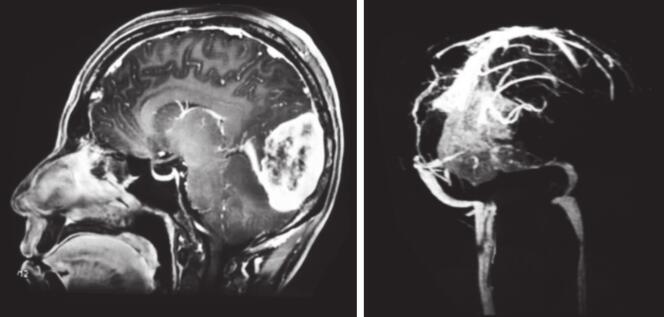

图3 术后CT示窦汇区术后改变,仍可见少量钙化影

图4 术后头颅MRI

MRI提示后颅窝术后改变,窦汇和右侧横窦显示不清